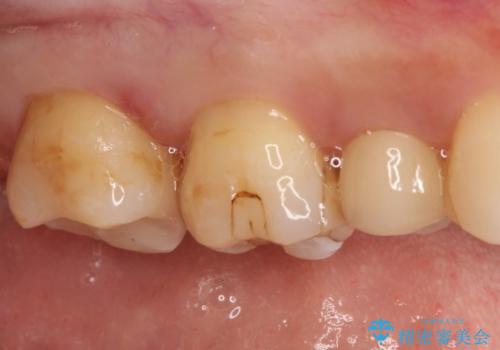

【セラミックインレー】虫歯の治療

- 虫歯を認めたため、セラミックインレーにて治療を行いました。

見た目も綺麗に修復することができ患者様には満足していただきました。

セラミックインレーの接着には必ずラバーダム防湿を行なっています。